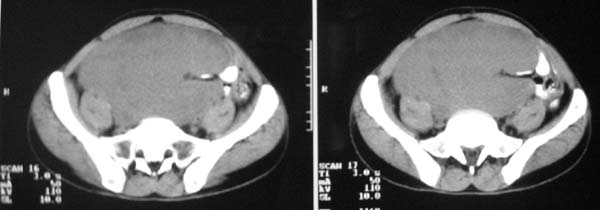

以下是引用zjzjr在2007-9-27 22:20:00的发言:[br]肠腔受推移,未见明显扩张及液平,所以考虑是肠外病灶, 间叶源性肿瘤?脂肪瘤?建议增强。